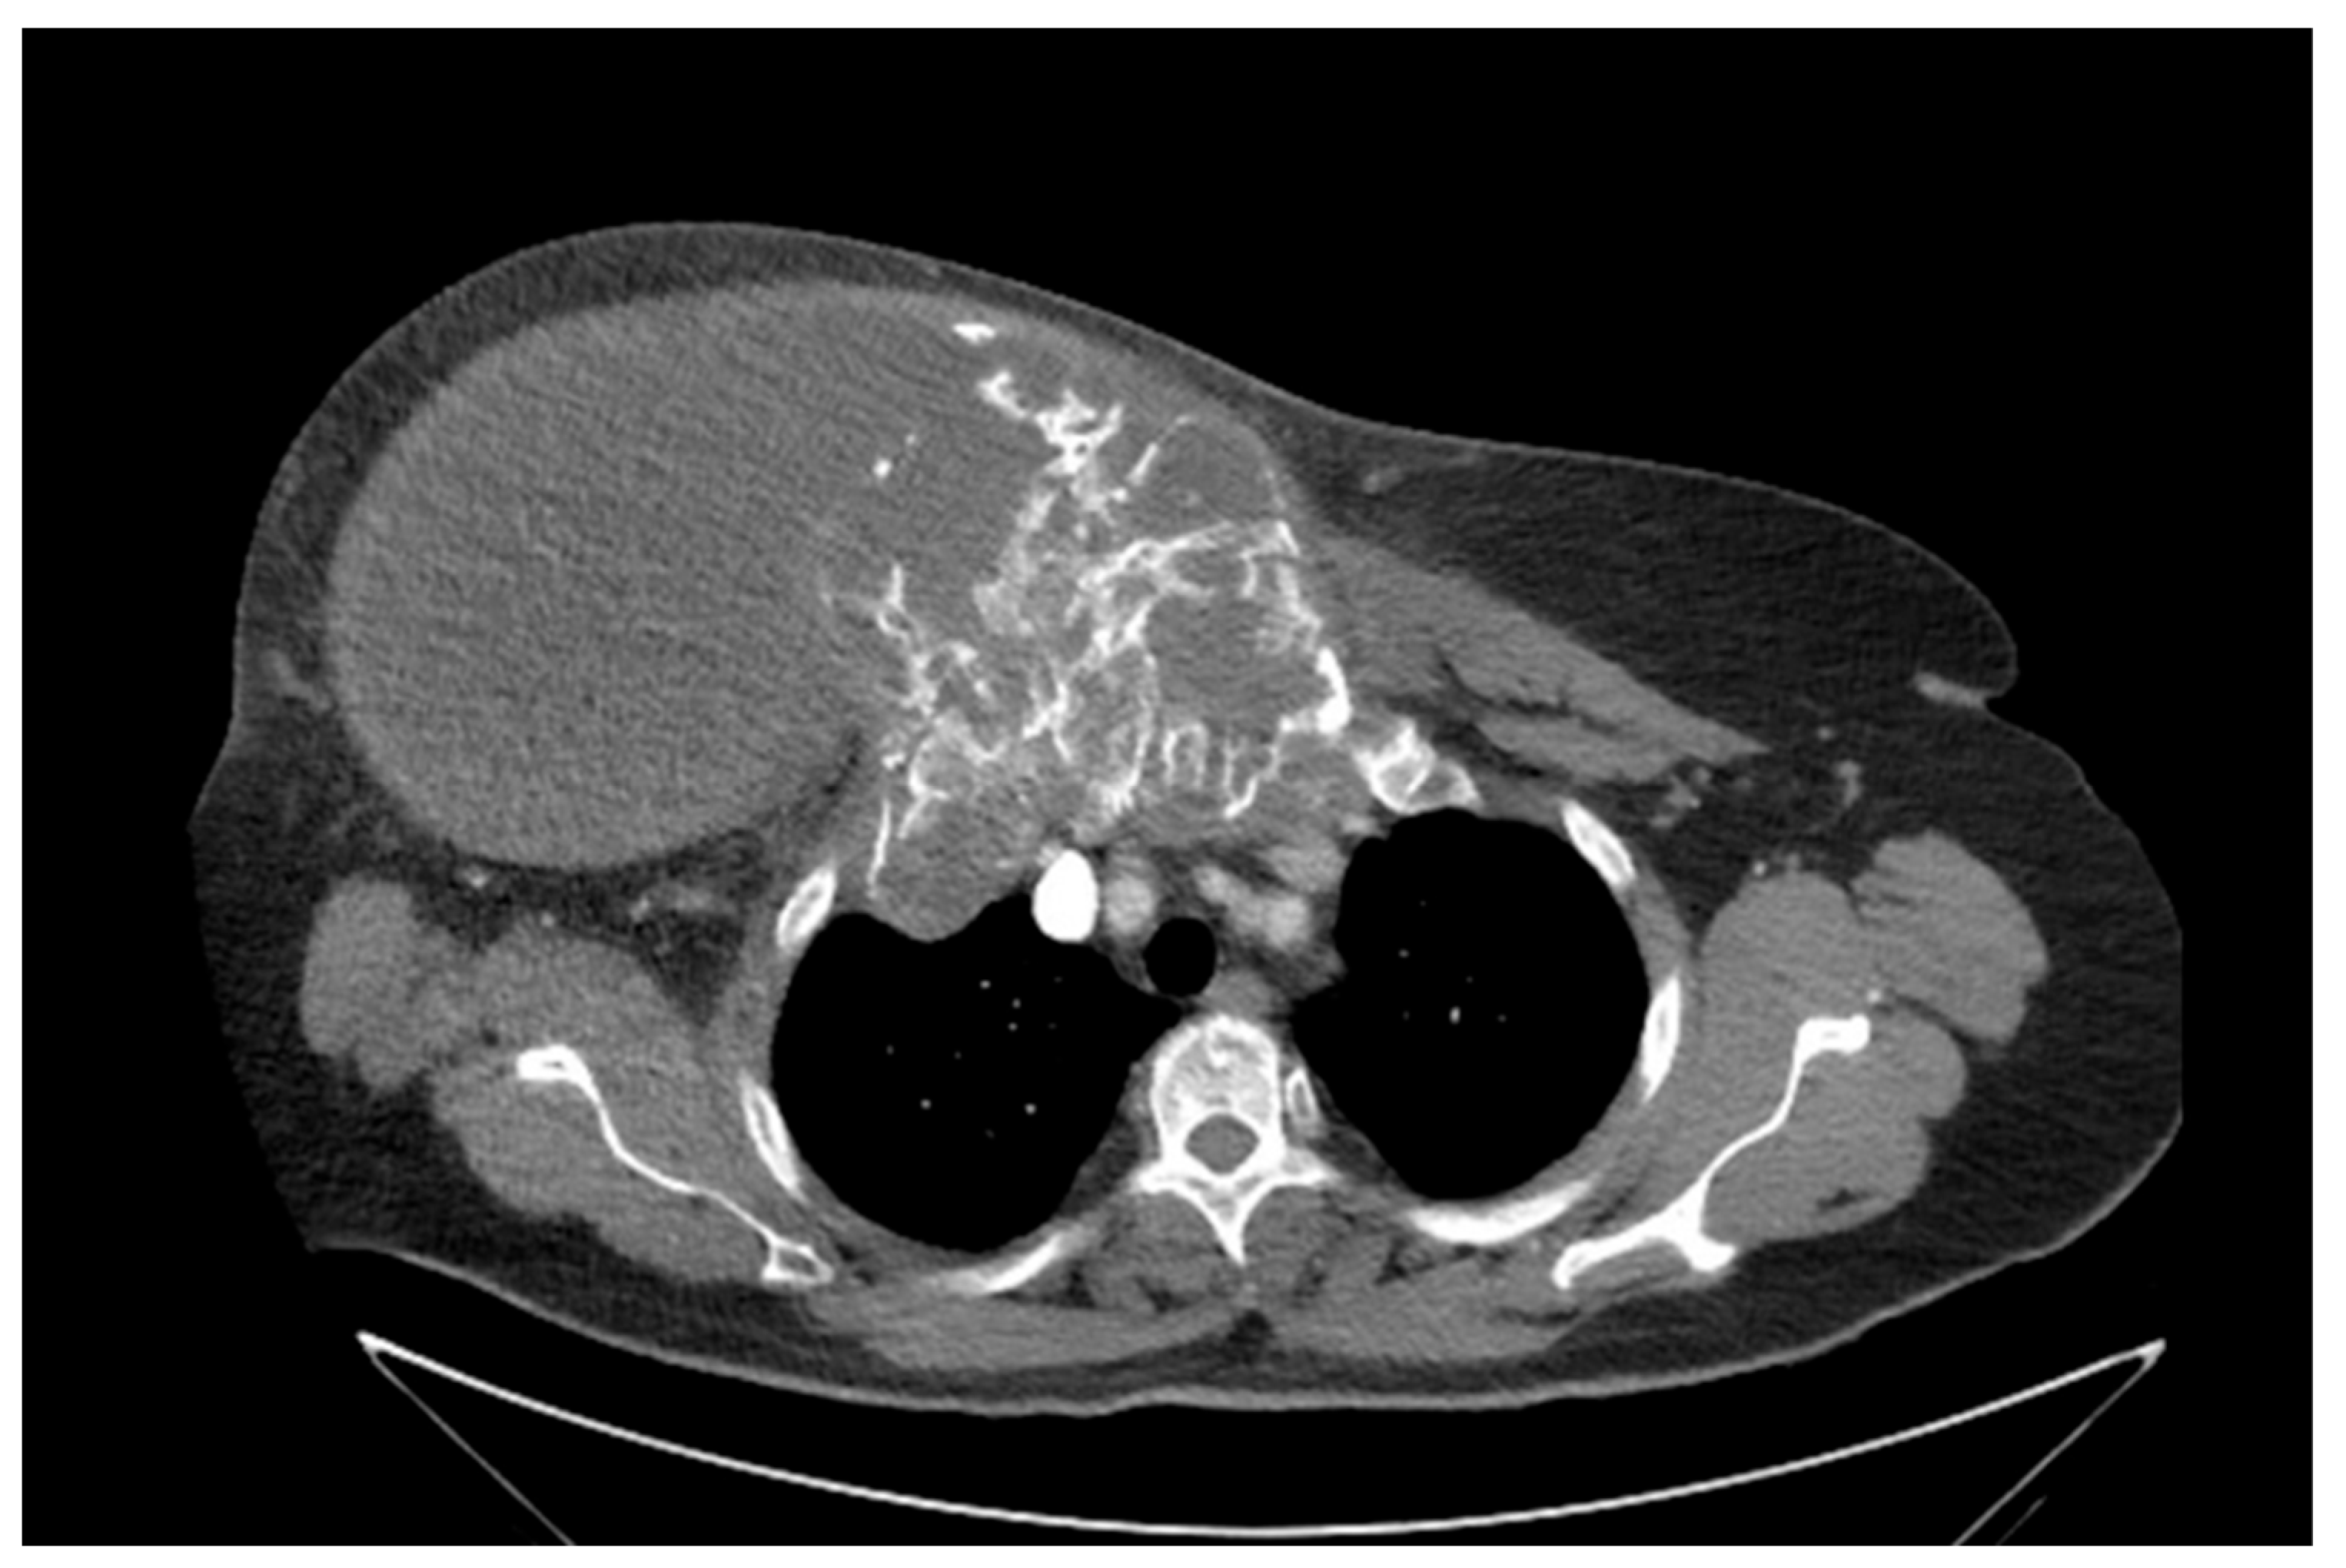

She returned to Bochum in June 2018 with the following symptoms: on the right ventral chest wall, she had a large tumor with a perforation in the pericardium of approximately 15 × 20 cm, an abdominal inguinal tumor on the right, and an ulcerating tumor on the lower left side of the abdomen. A computed tomography of the thorax and abdomen was performed in 09/2018 (Figure 2 and Figure 3) and a magnetic resonance imaging of the thorax was performed in 06/2018 (Figure 4 and Figure 5).

Figure 2.

Computed tomography of thorax and abdomen (CT Thx/Abd) in 2018. In this study, we detected a large tumor on the right anterior thorax with calcifications and invasion in the mediastinum.